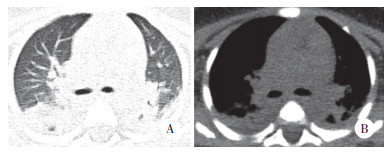

入院时实验室检查结果显示,(1)血常规:白细胞17.9×109/L,中性粒细胞百分比65.9%,淋巴细胞15.2%,血红蛋白69 g/L,血小板82×109/L;C反应蛋白69.60 mg/L;降钙素原13.75 ng/mL;D-二聚体6823 μg/L;(2)肝功能:白蛋白20.0 g/L,丙氨酸氨基转移酶98 U/L,门冬氨酸氨基转移酶58 U/L,氨基末端B型利钠肽前体 > 35 000 pg/mL;铁蛋白1 058.1 ng/mL;(3)入院后腰椎穿刺,脑脊液压力12 cmH2O。脑脊液常规检查:白细胞61×106/L,中性粒细胞16.3%,单核细胞83.7%。脑脊液生化结果:糖4.9 mmol/L,蛋白2.18 g/L。骨髓穿刺未观察到噬血细胞。免疫球蛋白、抗链球菌溶血素O(anti-streptolysin O,ASO)、血细菌培养无异常。(4)影像学检查:胸部CT,双肺多叶段炎症,部分肺组织实变。双侧胸腔积液(图 1A、1B)。颈部淋巴结彩超,双侧颈部淋巴结可见,左侧较大者1.2 cm×0.4 cm,右侧较大者1.1 cm×0.3 cm。头部CT(图 2)及心脏彩超无明显异常。

| 图 2 患儿入院第1天头部CT |